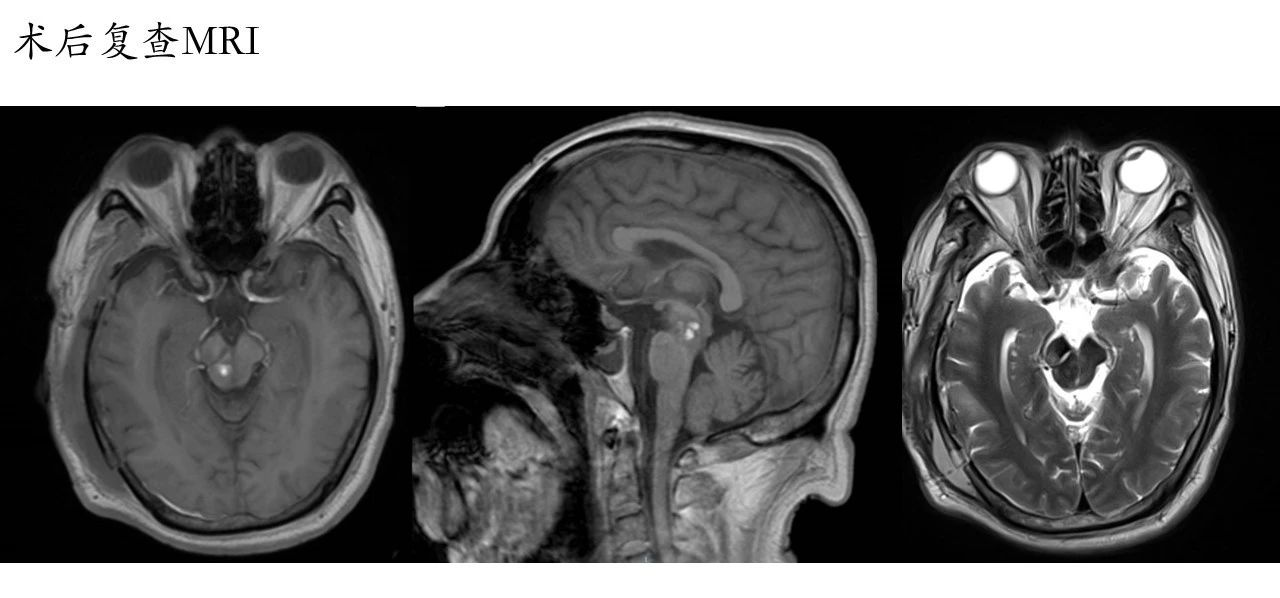

在术后给予患者给予抗血管痉挛、抗癫痫、脱水降颅压等药物治疗。术后第一天复查头颅CT,显示环池受压有改善,脑沟消失,侧裂仍有血肿,较术前减少(为减少侧裂血管骚扰,侧裂血肿的清除没有追求彻底的影像学完美)。术后行腰大池引流术引流血性脑脊液。